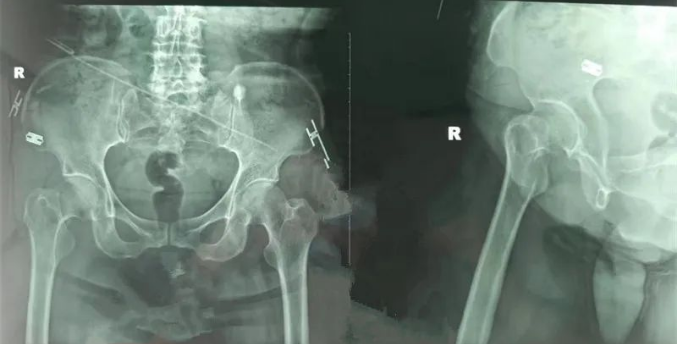

创伤科主任李培龙表示:对于年龄小于60岁的患者,无论骨折移位程度多大,闭合或切开复位内固定技术仍为目前首选。在内固定方式上,目前主流方式为空心钉内固定术,但其抗旋转、防退钉方面表现明显不如目前新的内固定方式——FNS股骨颈动力交叉钉系统。

FNS股骨颈动力交叉钉系统示意图

FNS是一种新型股骨颈内固定系统。临床研究显示FNS内固定系统的生物力学强度是传统“三根钉”结构的两倍,能为股骨颈骨折病例提供良好的抗旋,抗压功能固定效果可靠。